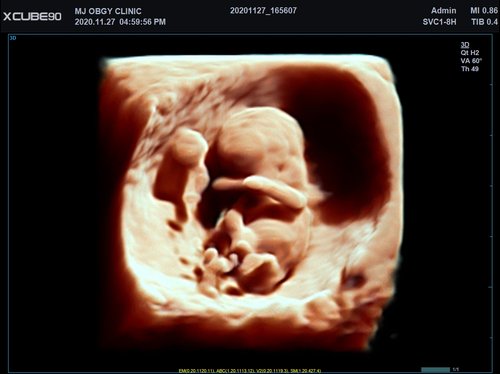

Mit dem X-CUBE 90 beginnt ALPINION eine neue Generation an Farbdopplersystemen, die X- CUBE Serie. Mit Bildverarbeitungstechnologien eines Premiumsystems und neuen Breitband- Schallköpfen mit X + Crystal Signature™ Technologie wartet das neue X-CUBE 90 auf.

X + Architecture

Die X + Architecture ist eine erstklassige Imaging-Plattform, die durch die Kombination von X + Crystal Signature™, der Schallkopftechnologie mit hoher Sensitivität und Breitbandigkeit, und X + FIT, ALPINIONs modernste Beamforming- und Datenverarbeitungstechnologiengeschaffen wurde. X + FIT ist eine neue Technologie, die den Schallstrahl scharf fokussiert sendet, ein großes Datenvolumen empfängt und mit hoher Geschwindigkeit verarbeitet. Darüber hinaus nutzt X + Crystal Signature™ Einkristalle und unser eigenes entwickeltes Schallkopfmaterial, um eine hervorragende Brillanz zu erzielen und die Diagnosemöglichkeiten zu erweitern.

• SVC1-8H (1-8 MHz) für Ultraschalluntersuchungen in Bereichen Abdomen, Geburtshilfe, Gynäkologie, Urologie, Pädiatrie, EM